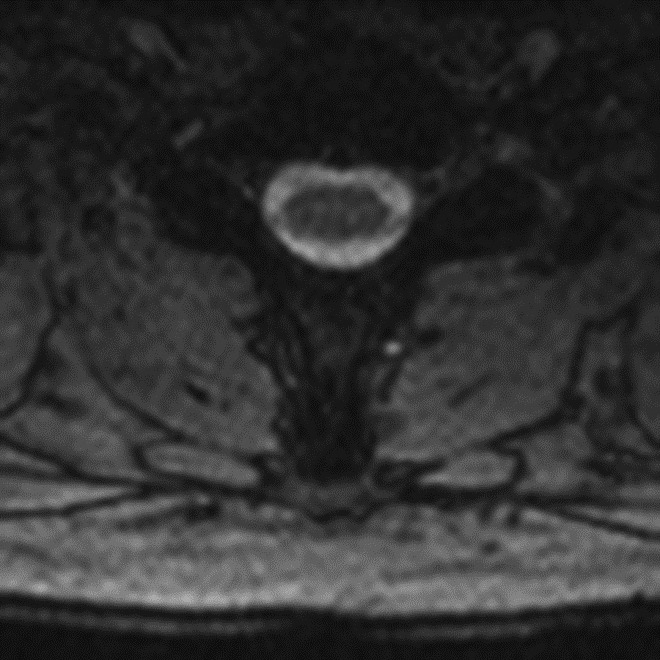

Truncation Artifact. (B) Corresponding axial MEDIC (multi-echo data image combination) MR image demonstrates normal appearance of the spinal cord.